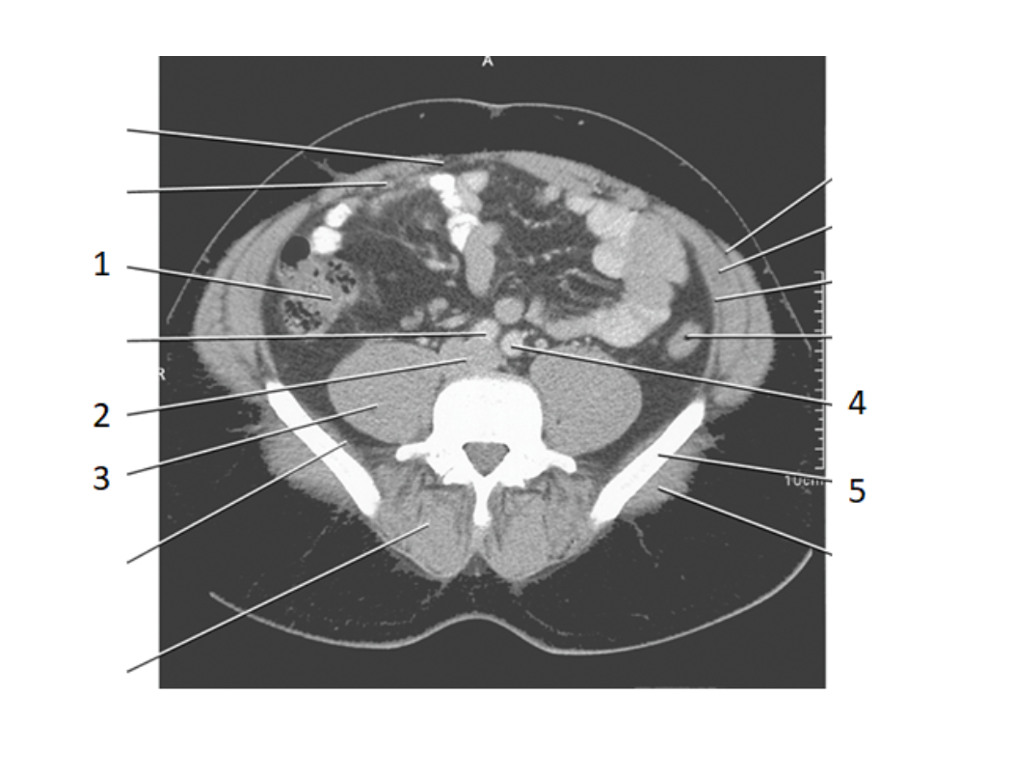

2

aorta

6

ilium

4

left common iliac artery

3

ureters

8

psoas

IV

11

celiac axis

12

splenic artery

15

portal vein

20